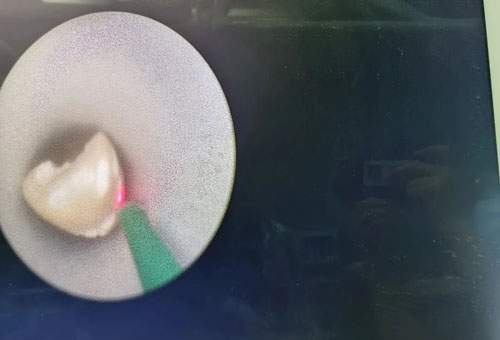

經(jīng)皮腎鏡鈥激光碎石取石中

在程廣舟副院長的指導(dǎo)下,程波副主任為患者實(shí)施手術(shù)。患者結(jié)石質(zhì)地堅(jiān)硬,碎石困難,在麻醉醫(yī)師與手術(shù)室護(hù)士的通力配合下,該患者順利完成雙側(cè)“無管化”經(jīng)皮腎鏡碎石取石術(shù)。從精準(zhǔn)穿刺到擴(kuò)張,再到手術(shù)結(jié)束,僅僅用了1個(gè)半小時(shí)。手術(shù)過程中,麻醉醫(yī)生密切觀察患者情況,術(shù)后患者順利復(fù)蘇,術(shù)后恢復(fù)良好,未出現(xiàn)發(fā)熱情況,術(shù)后復(fù)查腹部平片未見結(jié)石殘留,患者及家屬非常滿意。